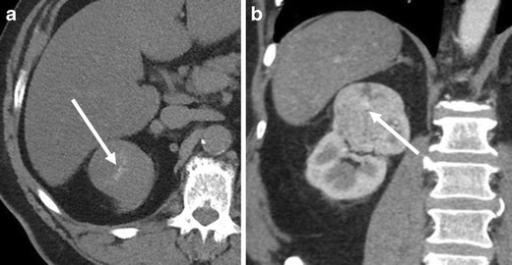

What's the Diagnosis?